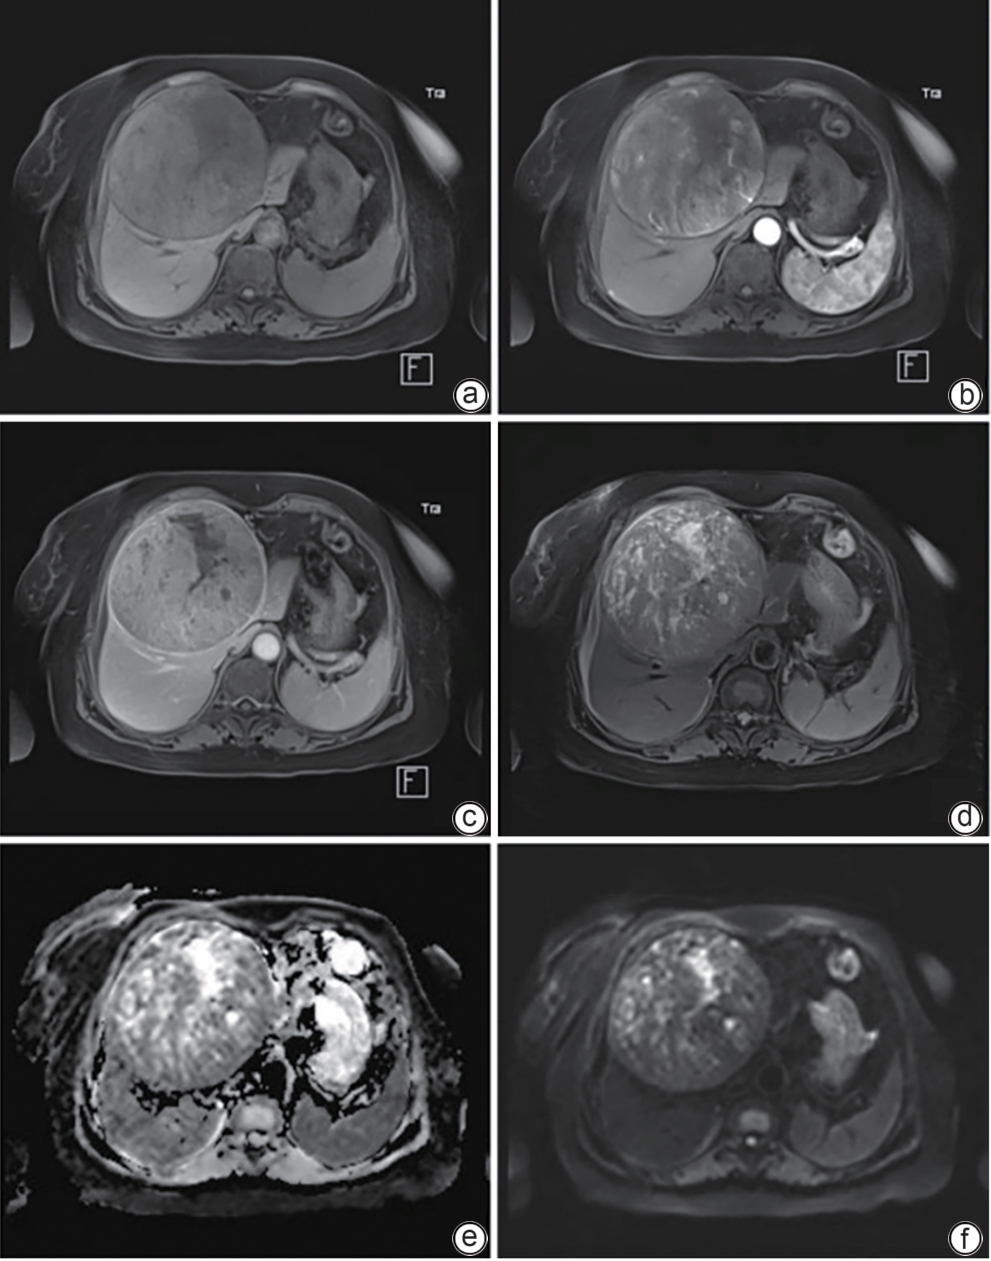

Liver Fibrosis and Liver Cirrhosis

Clinical and pathological features of patients with congenital hepatic fibrosis: An analysis of 26 cases

Shixuan LIU, Yujiao ZHANG, Ying ZHENG, Aiping SONG, Tailing WANG, Xiuhong WANG

2025, 41(11): 2317-2322. DOI: 10.12449/JCH251118

Abstract(102) HTML (25) PDF (2080KB)(43)

Abstract:

Objectives  To summarize the clinical and pathological features of patients with congenital liver fibrosis (CHF), and to investigate the differences in clinical and pathological features between patients in different age groups.  Methods  A retrospective analysis was performed for the clinicopathological data of 26 patients with pathologically confirmed CHF in China-Japan Friendship Hospital from August 2005 to June 2023, and the patients were stratified by age to investigate the clinical and pathological features of patients in different age groups.  Results  Among the 26 patients, there were 12 male patients and 14 female patients, with an age of onset of 4 — 61 years. There were 19 patients with portal hypertension type (73.08%), 2 patients with cholangitis type (7.69%), 4 patients with mixed type (15.38%), and 1 patient with occult type (3.85%). Of all 26 patients, 4 had unknown clinical symptoms, and among the 22 patients with clear clinical symptoms, 10 (45.45%) attended the hospital due to upper gastrointestinal bleeding caused by portal hypertension. Pathological manifestations included roughly normal liver parenchyma separated by fibrous septa in the portal area, with the presence of abnormal reactive bile duct hyperplasia. Denser fibrous septa and a lack of portal veins with the corresponding caliber were observed in 4 pediatric patients with disease onset before the age of 10 years, with a significant reduction or even disappearance of compensatory thin-walled blood vessels.  Conclusion  Portal hypertension-type CHF is the most common type in clinical practice. Patients with an early age of onset have certain histopathological features of the liver, with the presence of serious complications associated with portal hypertension. Therefore, liver biopsy should be performed for patients suspected of CHF in clinical practice, and genetic testing should be performed when necessary. Early identification and diagnosis are of great importance for improving the prognosis of patients.